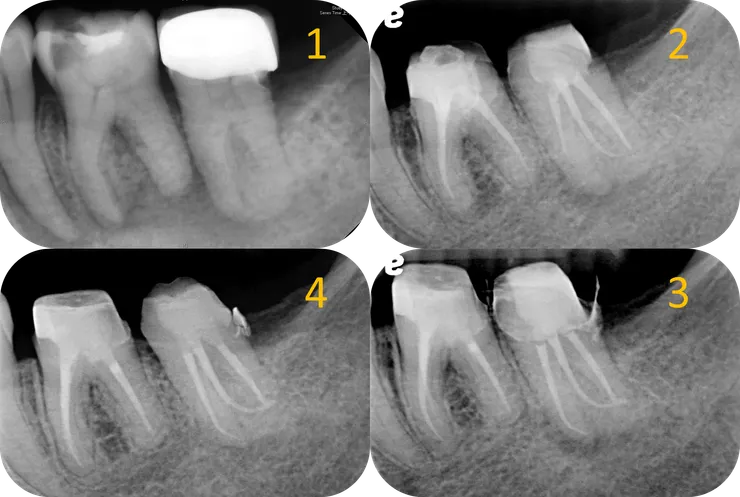

總結這兩顆的治療歷程:

1. Initial.

2. 第一次 RCF 後過了六年,36 distal apical lesion 顯著 healing.

3. 我接手後,歷經一年九個月,12 個 appointment 的治療,完成了這兩顆的 retreatment.

4. 一年後的追蹤,36 & 37 的 apical lesion 皆顯著癒合。

最後來檢討一下治療結果:

比較 DB canal 以及 MB & MB2 canal, 可以發現 DB canal 的修形相對保守許多。

其實以這顆的初始條件看來,MB & MB2 的修形是可以更加保守的......

然而逝者已矣,失去的齒質就再也回不來了......

若是在一開始治療前,就可以好好地把這顆的 root form & canal path 如中圖那般好好地描摹出來 (有 CBCT 則更好!),就可以以終為始地,依據每個 canal 的型態, 分別打造出最恰到好處的入口修型!如此一來,就可以在大幅縮短治療時間的同時,也保留更多齒質!